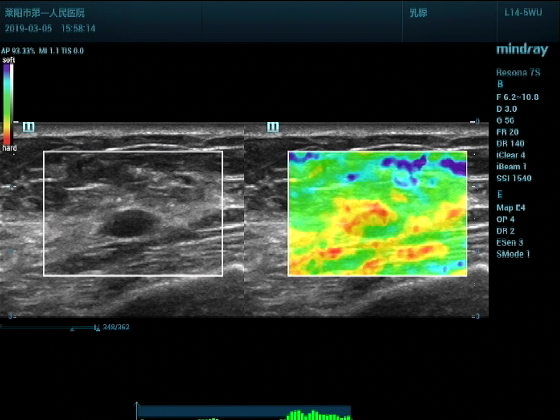

超声入门贴994--乳腺纤维瘤(弹性成像)